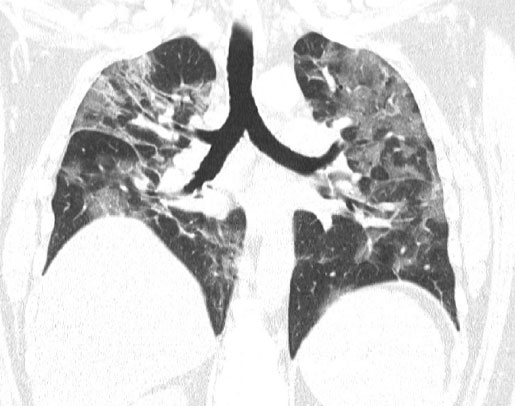

A tomografia de pulmão abaixo é de um paciente de 40 anos de idade, e foi tirada 6 semanas após a infecção pela COVID-19. Apesar do esforço (5 agachamentos) e se sentindo confortável, há uma diminuição da saturação de oxigênio como sinal de uma shunt pulmonar. Na imagem é possível identificar consolidações e infiltrações em ambos os lados.

Mesmo sendo considerados pacientes recuperados, inicialmente eles não podem mergulhar mais, pois apresentam danos irreversíveis nos pulmões, onde em alguns casos, foram identificadas consolidações maciças e infiltrações.

“A tomografia dos pulmões mostrou que não houve uma melhora significativa”, disse Hartig.

Ainda segundo o médico, dois pacientes apresentaram deficiência significativa de oxigênio quando estavam sob estresse pulmonar, aspecto típico de shunt pulmonar persistente. Os brônquios ainda se apresentam muito sensíveis quando estressados, assim como ocorre nos asmáticos.